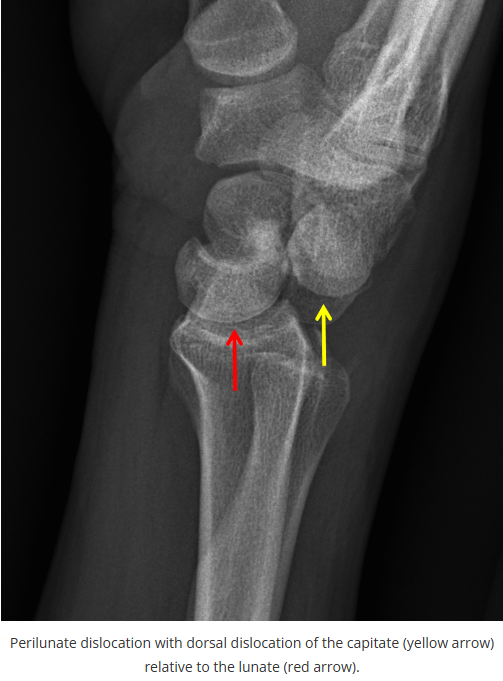

这些腕与手的骨折X线片如果没有标注箭头,你还能识别出来吗?

X线读片是骨科医生的基本功。

今天是腕部与手的X线片。所有X线片都

带有标注和说明

,可以选择长按图片,

自动翻译相关说明